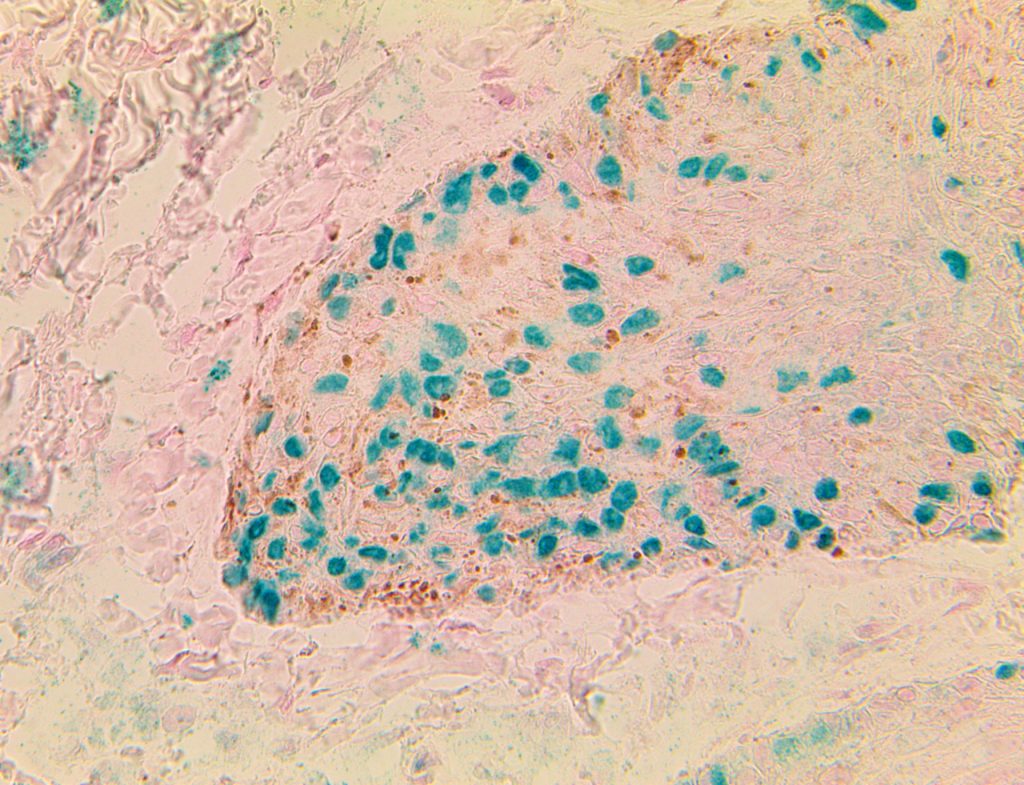

Bio SB has developed high affinity IVD monoclonal antibodies for fast immunohistochemistry (IHC) detection of melanoma, basal cell carcinoma (BCC), squamous cell carcinoma (SCC) and other Mohs surgery related conditions. Combined with our innovative IHC detection systems, we are opening the doors to a faster and more accurate immunohistochemistry applicable to Mohs surgery.

Bio SB has developed a fast, non-biotin monovalent Fab micropolymer IHC detection system for the detection of IVD antibodies for melanoma, BCC, SCC and other Mohs surgery related conditions. Our innovative IHC detection systems have opened the doors for a faster and accurate immunohistochemistry applicable to Mohs surgery.